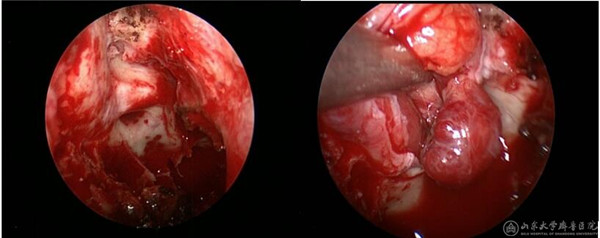

(手术过程,显露右侧视神经及眶筋膜,然后将肿瘤自眶内完整取出)

(术后可见右眼眶内肿瘤完整切除,视神经无受压,眶内正常结构未破坏)